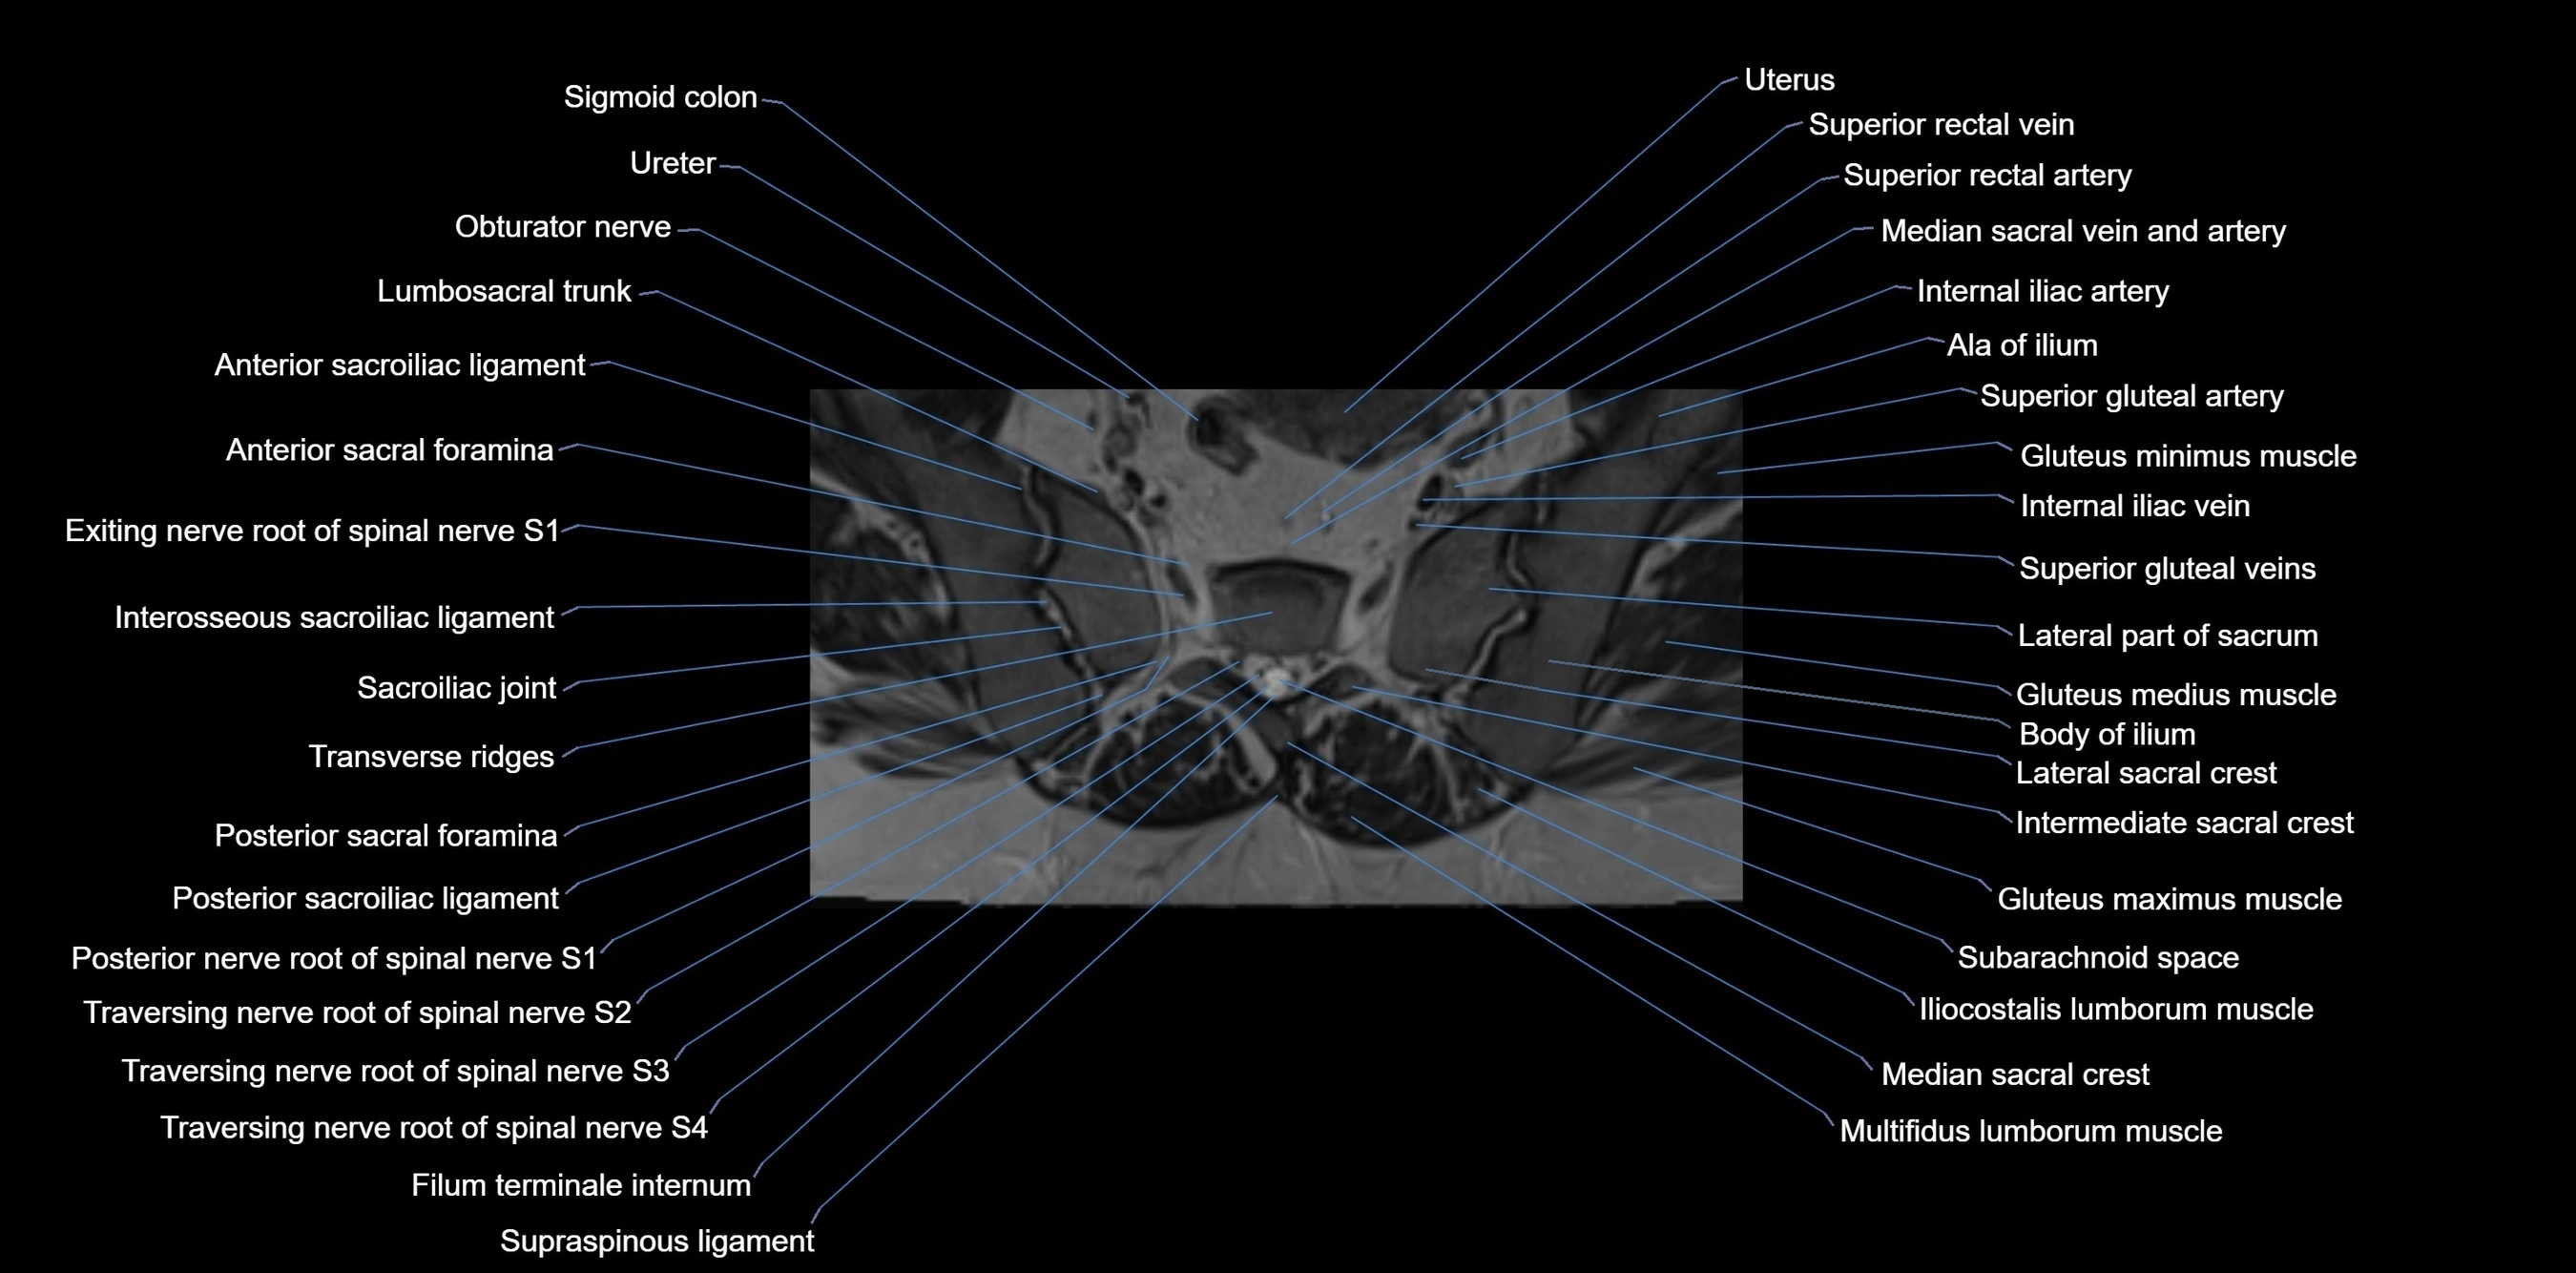

MRI image

image